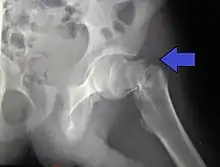

X-rays of the affected hip usually make the diagnosis obvious; AP (anteroposterior) and lateral views should be obtained.

Intracapsular fractures

For low-grade fractures (Garden types 1 and 2), standard treatment is fixation of the fracture in situ with screws or a sliding screw/plate device. This treatment can also be offered for displaced fractures after the fracture has been reduced.

Fractures managed by closed reduction can possibly be treated by percutaneously inserted screws.[37]

In elderly patients with displaced or intracapsular fractures surgeons may decide to perform a hemiarthroplasty, replacing the broken part of the bone with a metal implant.[38] However, in elderly people who are medically well and still active, a total hip replacement may be indicated. Independently mobile older adults with hip fractures may benefit from a total hip replacement instead of hemiarthroplasty.[39]